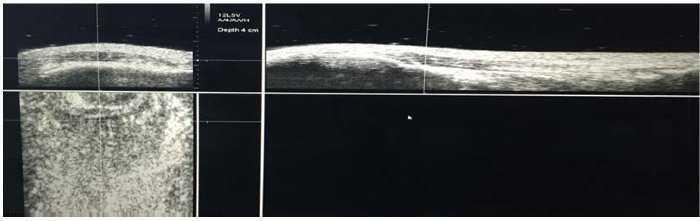

Todas las valoraciones se hicieron durante la mañana de inicio de la pretemporada, los jugadores en edades formativas el día 18 de agosto, y los jugadores profesionales el 25 de agosto. Se realizó exploración por el mismo experto en ultrasonografía y UTC (GH) de ambos tendones rotulianos mediante ecografía en modo B con un transductor lineal de 7-10 MHz (SmartProbe 10L5; Terason 2000, Teratech, EE. UU.) montado sobre el dispositivo que mueve el transductor de forma automática en el eje perpendicular del tendón y que graba las imágenes transversales a intervalos de 0,2 mm sobre una distancia de 12 cm (600 imágenes axiales) (fig. 1). El dispositivo estandarizó el ángulo de inclinación de la sonda, la ganancia, el foco y la profundidad. La captura de las imágenes y las mediciones de UTC se realizaron siguiendo un protocolo estandarizado, aplicado en otros estudios6.

Figura 1 Aparataje utilizado para la realización de las medidas. UTC device.

El jugador se posicionó sentado con la rodilla flexionada a 90¿ y con el pie apoyado en una superficie elevada. El dispositivo se colocó paralelo al eje largo del tendón rotuliano desde su inserción distal en la tuberosidad tibial anterior hasta su inserción proximal en el polo inferior de la rótula. Se aplicó gel entre la piel, el soporte de silicona y entre este y la sonda de ultrasonidos antes de realizar la exploración (fig. 2).